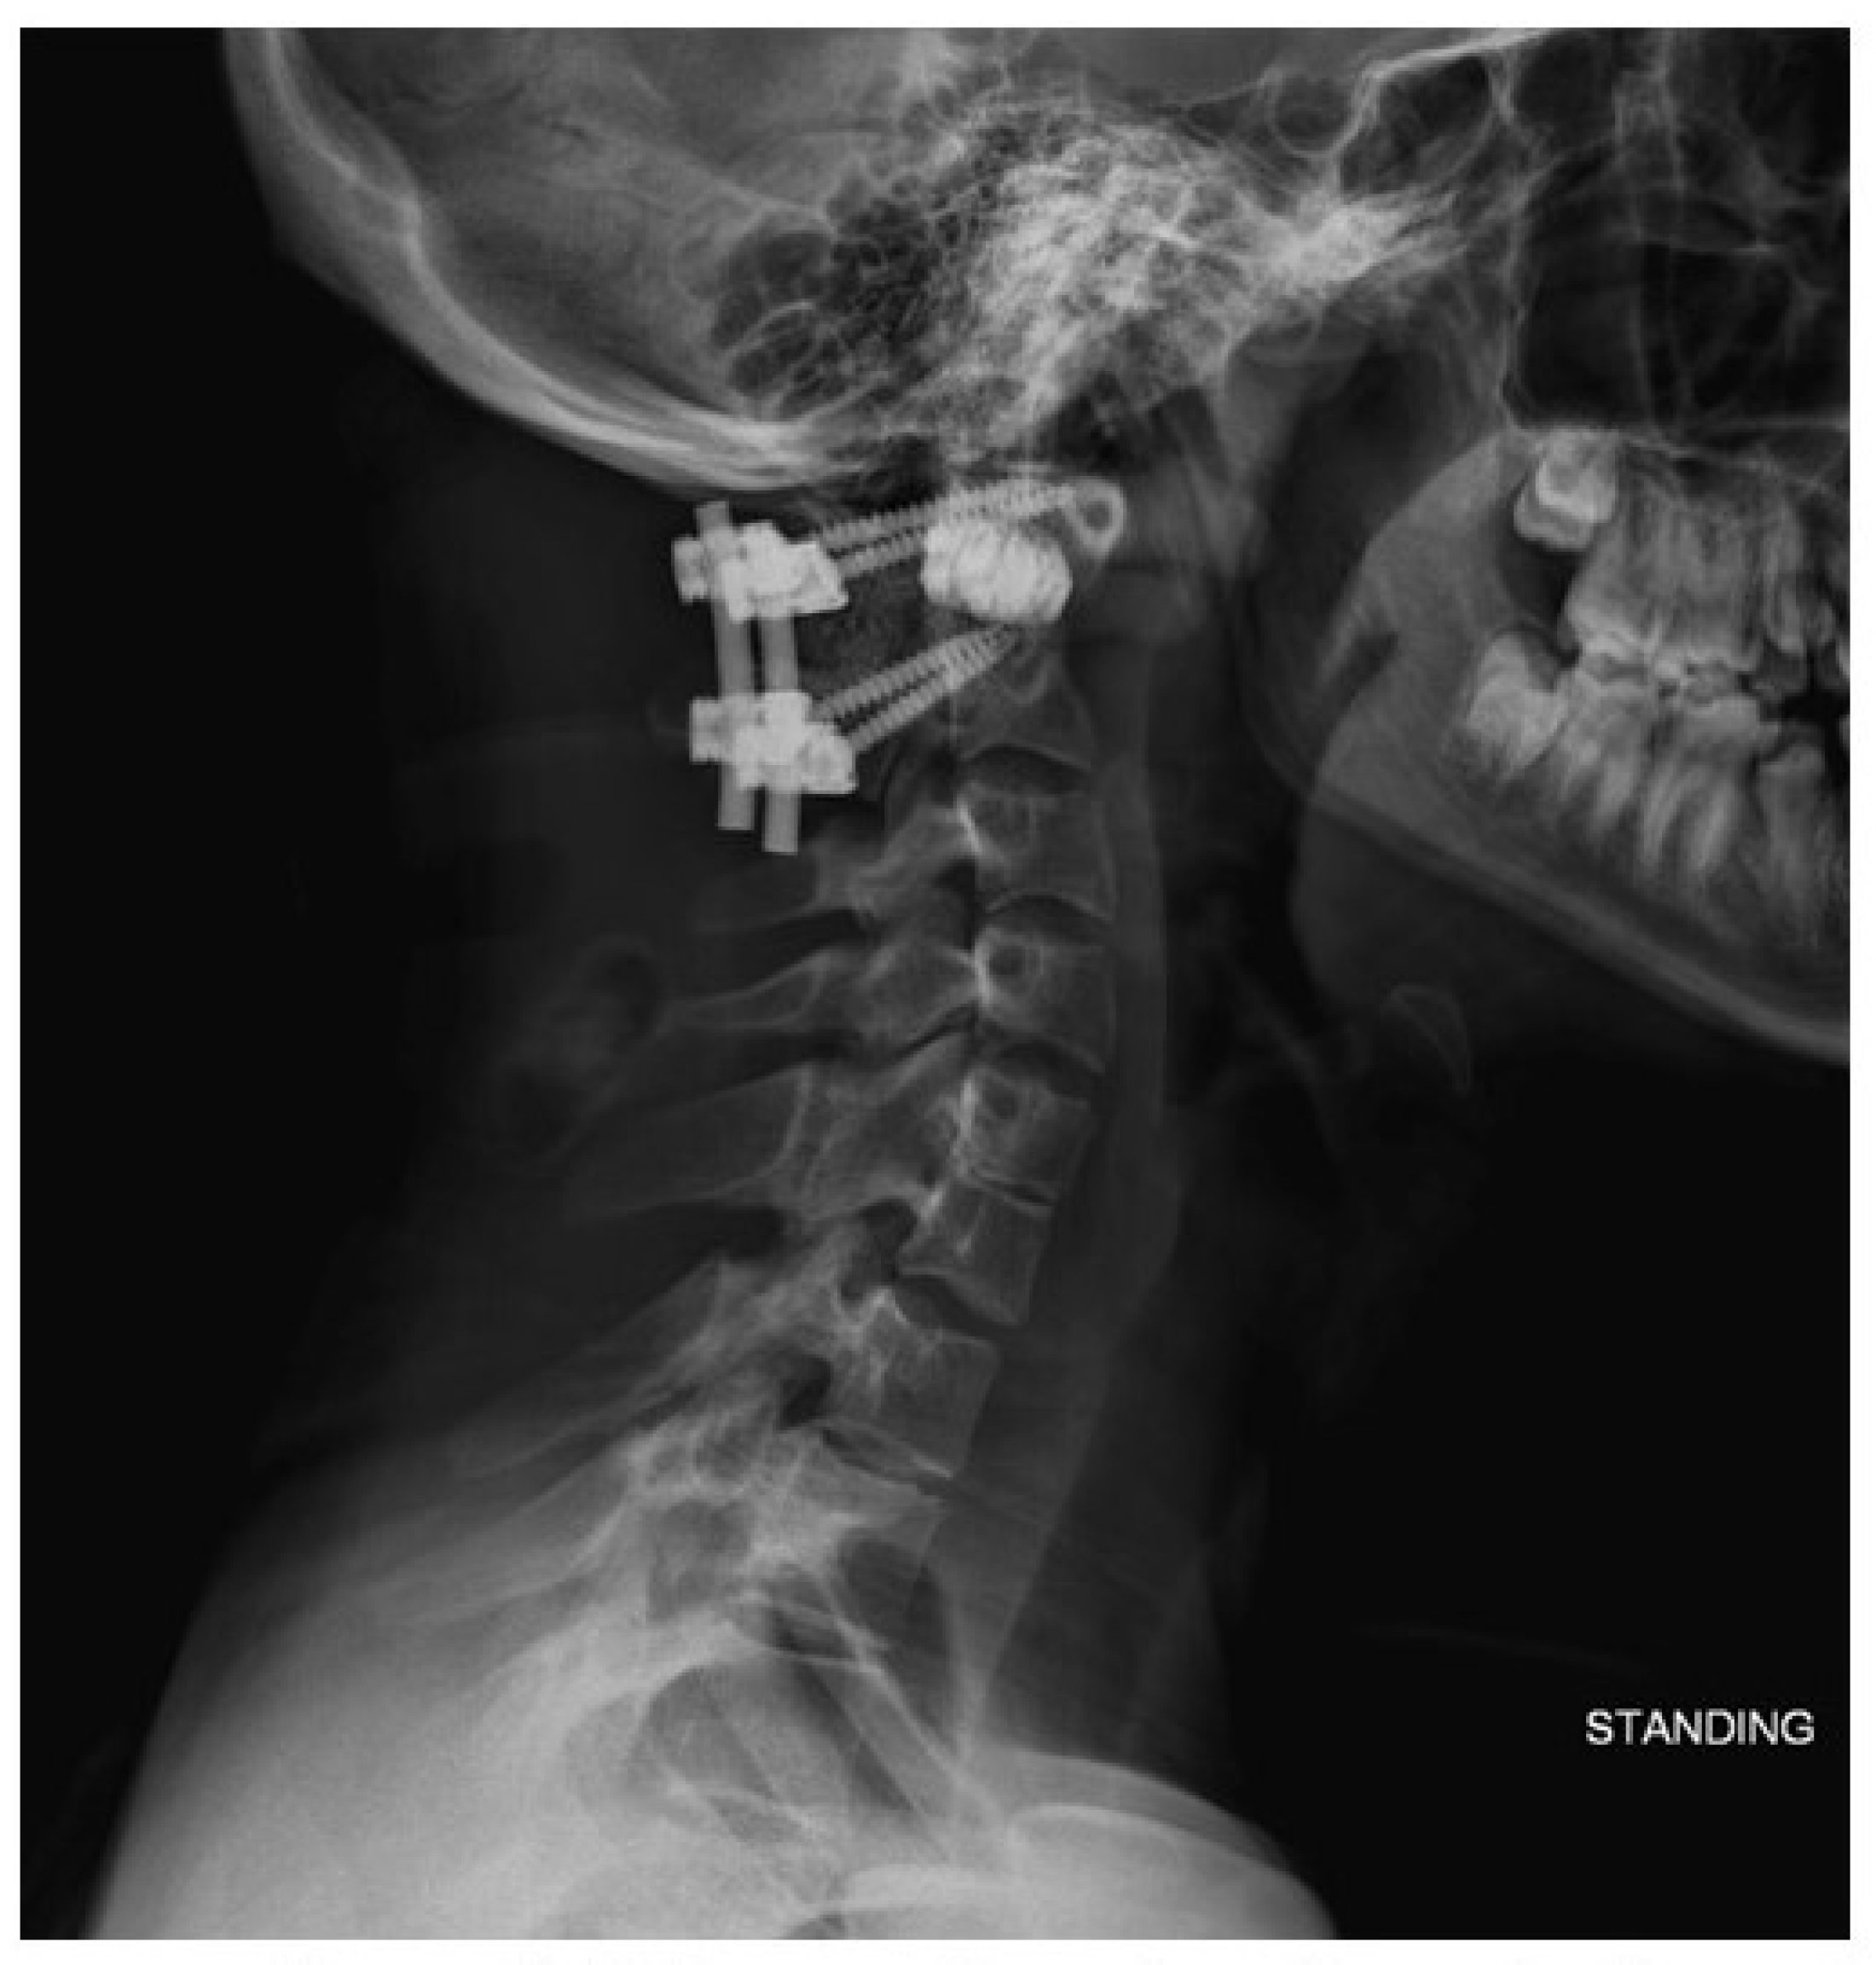

4. Results